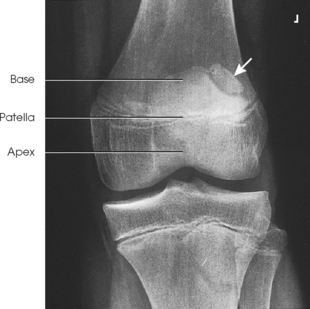

• Center the IR to the patella.

• Adjust the position of the leg to place the patella parallel with the plane of the IR. This usually requires that the heel be rotated 5 to 10 degrees laterally (Fig. 6-146).

Structures shown: The PA projection of the patella provides sharper recorded detail than in the AP projection because of a closer object-to-IR distance (OID) (Figs. 6-147 and 6-148).

Structures shown: The resulting image shows a lateral projection of the patella and patellofemoral joint space (Figs. 6-150 and 6-151).